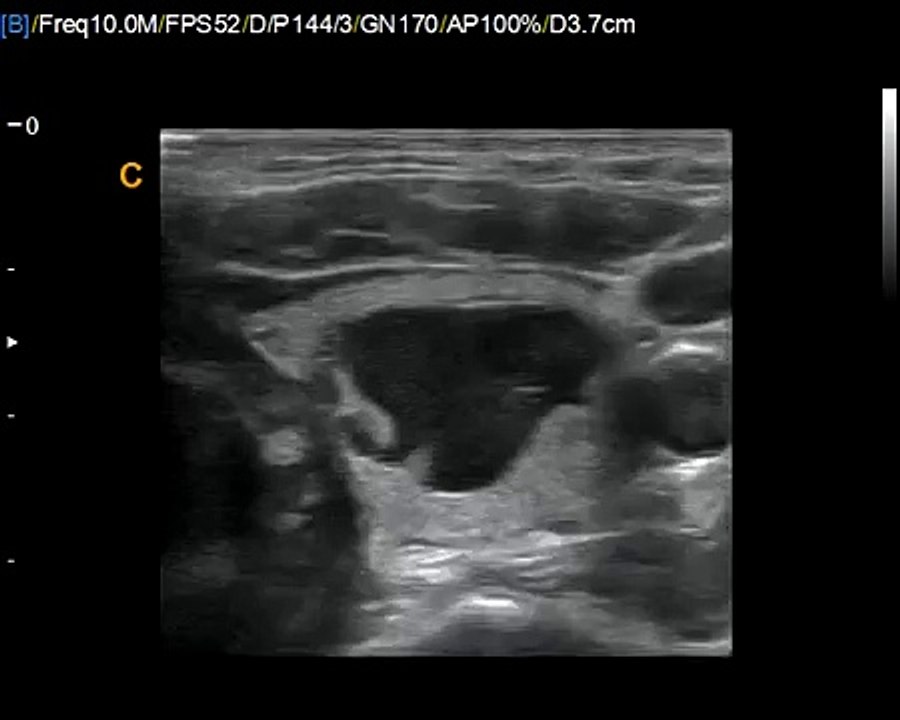

Chison Qbit Thyroid Image, one of best ultrasound for diagnostic examination of Thyroid disease 0:08

Chison Qbit Thyroid Image, one of best ultrasound for d...

Keebomed 3 views